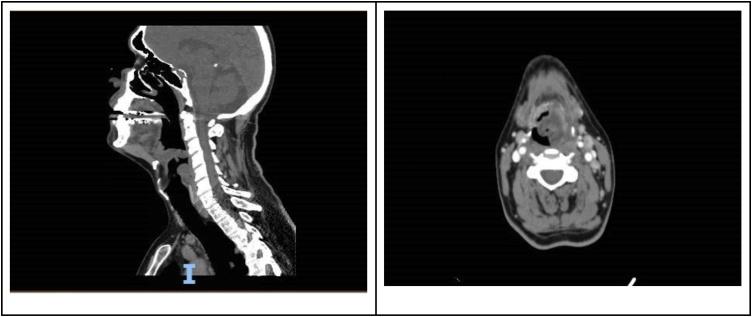

Epiglottitis is an uncommon, potentially fatal infection of the epiglottis that can lead to complete upper airway obstruction. Isolated pathogens are usually nasopharyngeal bacteria, most commonly type b (Hib). While the incidence of epiglottitis has diminished significantly over the years due to widespread vaccination against Hib, the proportion of epiglottitis caused by other pathogens has increased. In this report, we introduce an unseen presentation of acute epiglottitis associated with severe acute respiratory distress syndrome--coronavirus2 (SARS-CoV-2), who presented to the emergency department with throat pain and odynophagia that quickly resulted in respiratory distress. Clinicians should be aware of airway edema's concomitant presence in patients with acute epiglottitis and COVID-19 and maintain a low threshold for intubation. The rapidly progressive nature of COVID-19 and its complications may preclude intubation later on in the patient's clinical course, potentially necessitating an emergent surgical airway.

会厌炎是一种罕见的、可能致命的会厌感染,可导致完全性上呼吸道梗阻。分离出的病原体通常为鼻咽部细菌,最常见的是b型流感嗜血杆菌(Hib)。尽管近年来由于广泛接种Hib疫苗,会厌炎的发病率已显著下降,但由其他病原体引起的会厌炎比例有所增加。在本报告中,我们介绍了一例与严重急性呼吸窘迫综合征冠状病毒2(SARS-CoV-2)相关的急性会厌炎的罕见病例,该患者因咽痛和吞咽痛就诊于急诊科,很快就出现了呼吸窘迫。临床医生应意识到急性会厌炎患者与新型冠状病毒肺炎(COVID-19)患者同时存在气道水肿,并保持较低的插管阈值。COVID-19及其并发症的快速进展特性可能会使患者在临床病程后期无法进行插管,可能需要紧急建立外科气道。